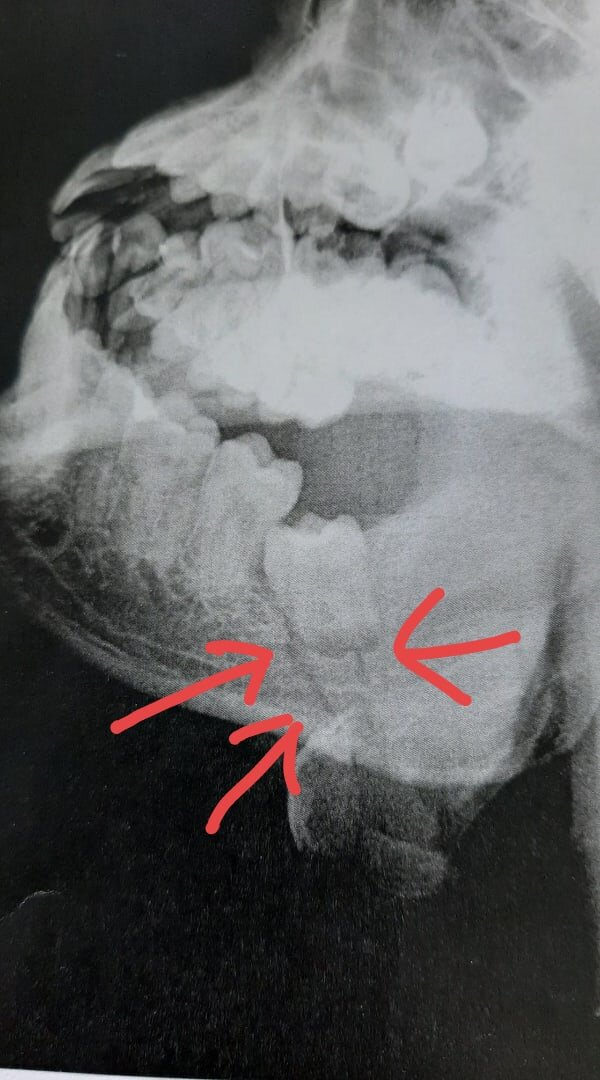

Первые пару дней после перелома для меня были разочарованием, т.к. челюсть ныла при любом повороте или движении, перелом находился в неудачном месте, под зубом мудрости.